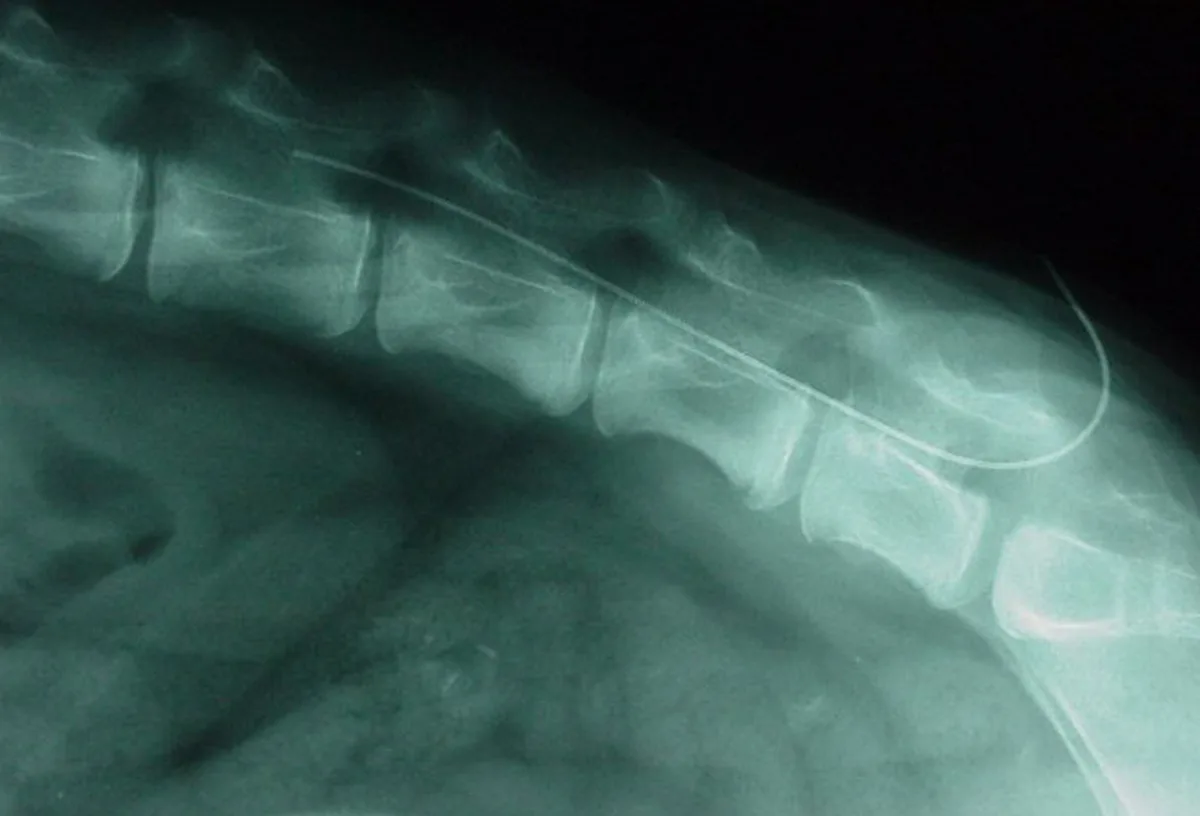

Because of the bluntness of the needle, it may be useful to make a small skin incision (using local anesthetic if the dog is awake). Location of landmarks and confirmation of placement are as described in Step 4, paying close attention to sterility. The catheter is threaded through the needle (Figure 6A), and the tip can be placed where it will be most beneficial-for example, as high as the 4th thoracic vertebra for fore limb amputation or thoracic surgery. The catheters have radio-opaque, measured markings to assist in correct placement (Figure 6B). An adaptor and a filter are applied to the end of the catheter to maintain sterility, and the catheter is secured by suturing to the skin. An adhesive covering keeps the site clean and offers additional security for the catheter (Figure 6C).